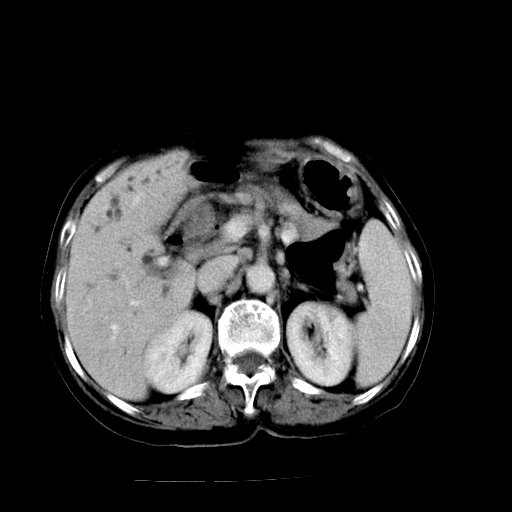

以下是引用随光逐影在2009-4-7 8:21:00的发言:[br]肝内外胆管多发性结石并肝内外胆管扩张;胆系感染。